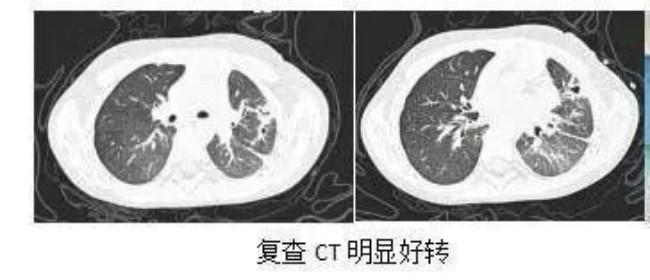

入院第6天,澄澄病情终于迎来拐点:复查胸片明显好转,呼吸机参数也成功下调,顺利拔掉气管插管,从有创呼吸机换成无创通气。经过2周的治疗,孩子病情顺利恢复,复查胸部CT显示肺部炎症和脓胸都明显好转,胸腔引流管也顺利拔除。从发热咳嗽到呼吸衰竭,从命悬一线到康复好转,澄澄的家人悬了十几天的心,终于彻底放下。家长特意制作锦旗,表达感激之情。